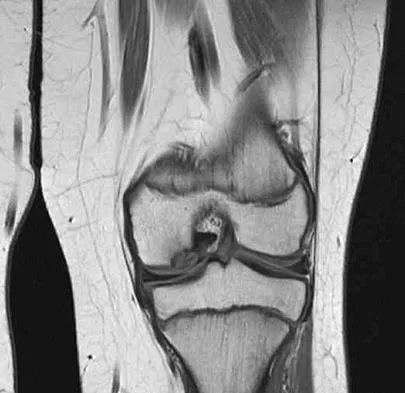

Figure 42 shows the sagittal T2-weighted MRI scan of a patient's right knee. These findings are most commonly seen with a complete tear of the

The MRI scan reveals disruption of the lateral capsule and ligaments with fluid in the soft tissues laterally. Additionally, there is a large bone bruise on the medial femoral condyle. This combination indicates injury to the posterolateral complex. These injuries often have coexisting anterior and/or posterior cruciate ligament injuries. Failure to recognize the posterolateral corner injury can lead to failure of anterior or posterior cruciate ligament reconstructions. LaPrade RF, Gilbert TJ, Bollom TS, et al: The magnetic resonance imaging appearance of individual structures of the posterolateral knee: A prospective study of normal knees and knees with surgically verified grade III injuries. Am J Sports Med 2000;28:191-199.